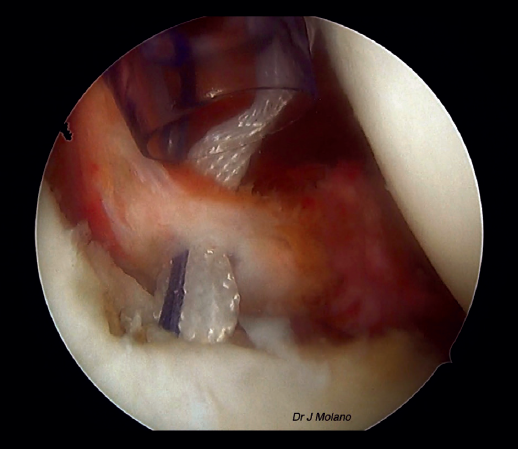

Una vez realizada la reparación de Bankart, se cambia nuevamente el artroscopio al portal anterosuperior y desde el posterior vamos recuperando los 2 cabos de cada sutura a nivel del Hill-Sachs para anudarlos, en el espacio subacromial, de inferior a superior (habitualmente 4 suturas), consiguiendo el relleno del defecto de Hill-Sachs.

Figura 7. Visión artroscópica desde el portal superior tras anudado de remplissage, implantación intraarticular de la ligamentoplastia y reparación capsulolabral que oculta el ligamento.